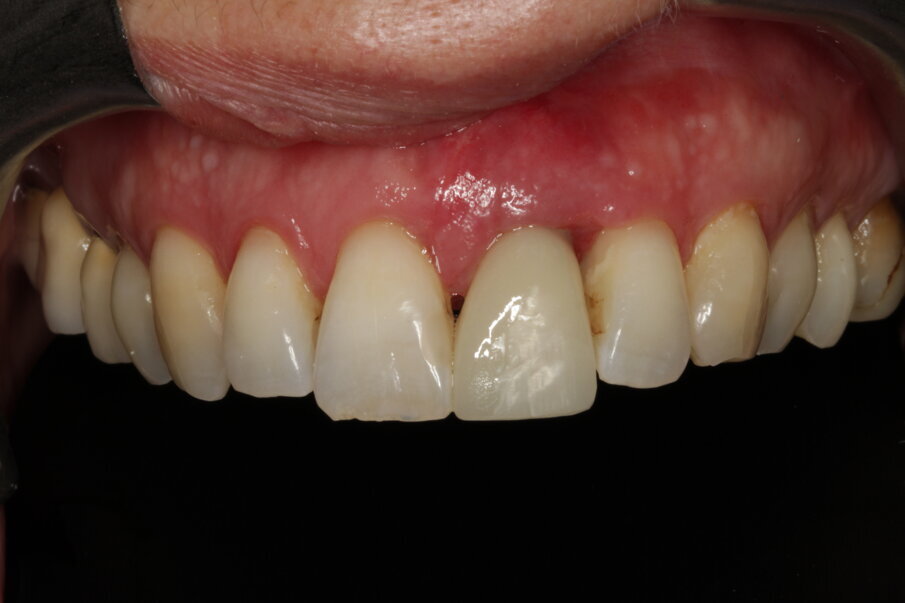

Tissue conditioning

As evidenced by the aesthetic analysis before treatment, it was clear that symmetry with the contralateral incisor would be impossible. The implant was placed slightly distal because the distal papilla normally has a narrower mesiodistal basis than the central papilla. The tissue volume augmentation helped to obtain the necessary quantity of gingiva to shape nice papillae, leaving a minimal gap. The soft tissue architecture was conditioned (Fig. 32) by adding composite to the temporary crown and grinding material where necessary until the prosthodontist and the patient felt an optimal result had been achieved.